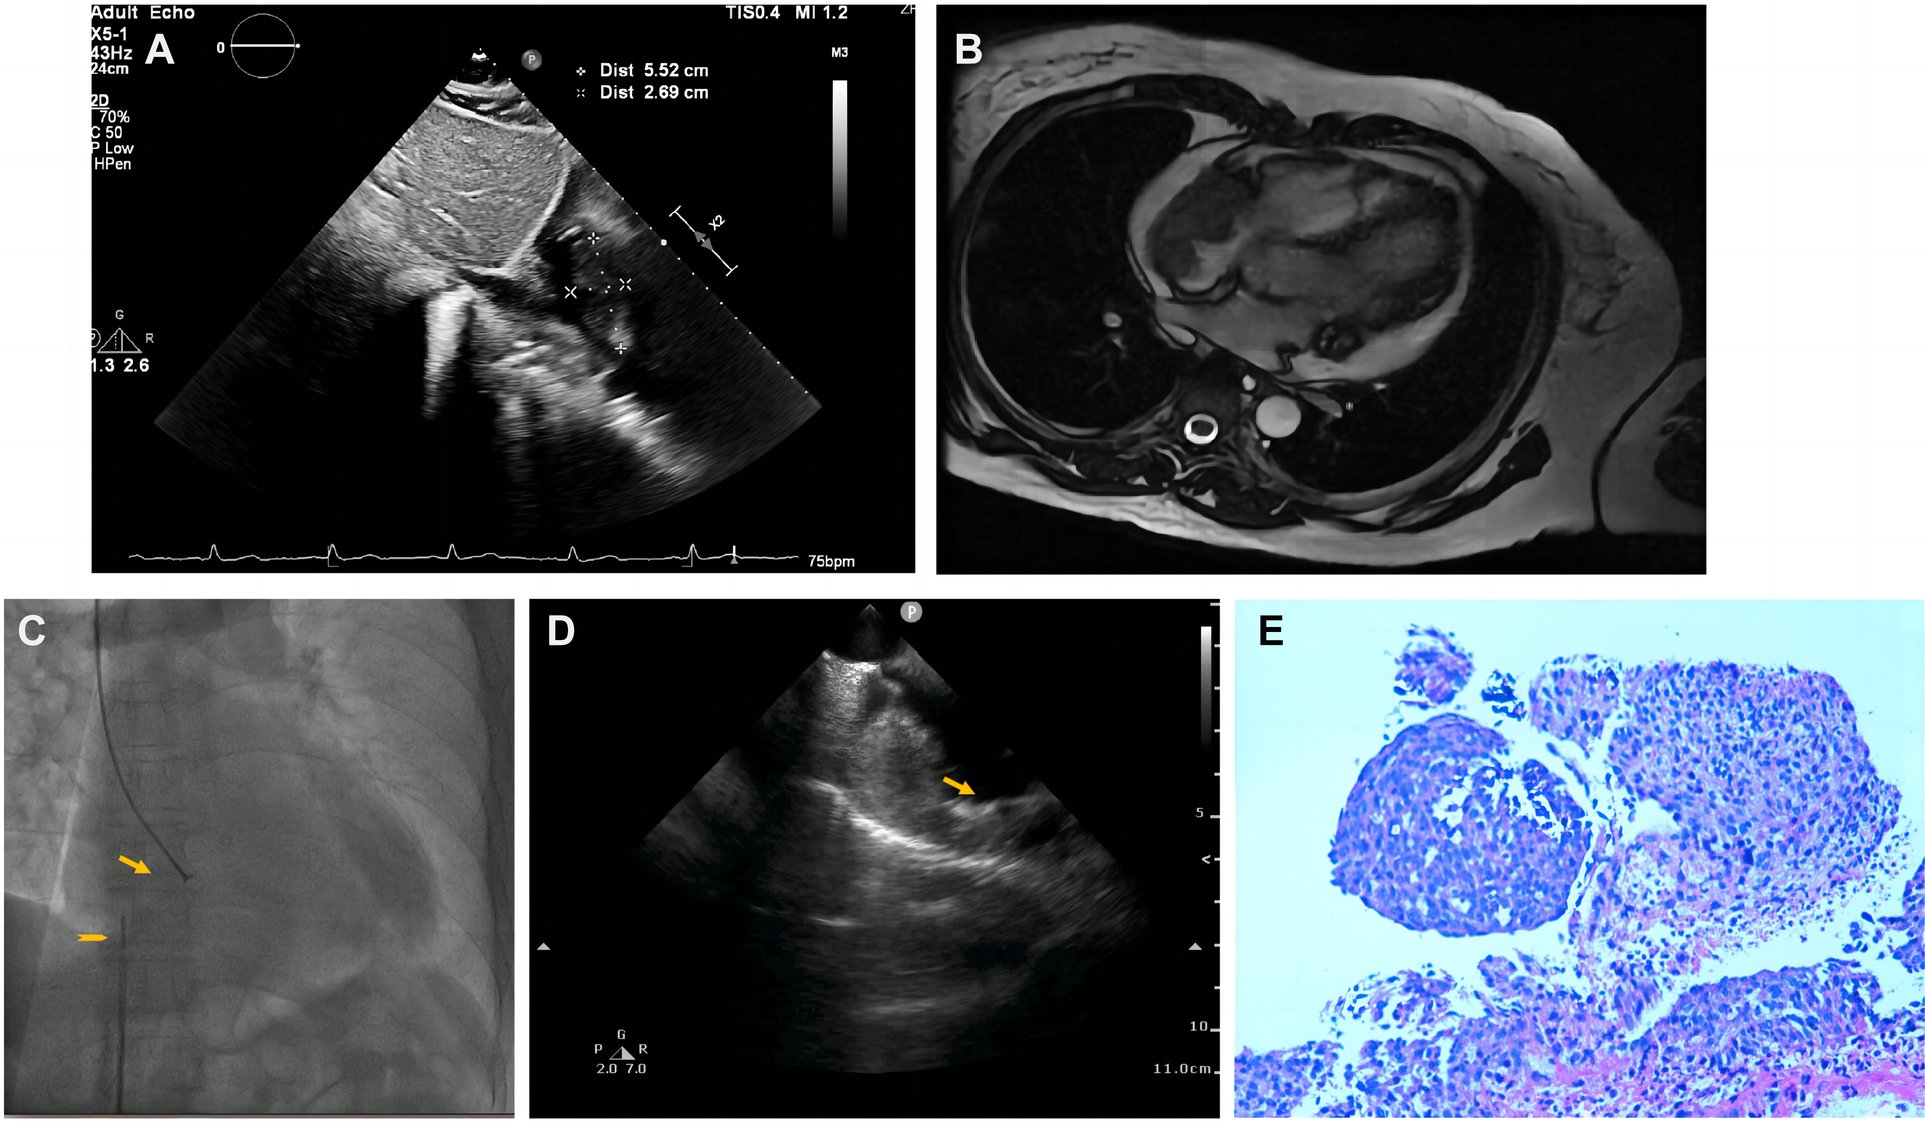

A 50-year-old woman, who had been experiencing shortness of breath and chest tightness for four months, was admitted to a nearby hospital. A chest computed tomography (CT) revealed enlarged heart with pericardial effusion as well as multiple lesions in lungs with suspected infection. CT-guided needle biopsy of pulmonary lesions was performed. Only heterozygous cells were found in the necrosis, and the pathological findings of the lung biopsy were unremarkable. After a few days, the patient gradually felt dyspnea and weakness. She was transferred to our cardiology department for a conclusive diagnosis. Blood testing showed high level of the C-reactive protein (CRP) (16.6 mg/L), pro-Brain natriuretic peptide level of 224 pg/mL, D-dimer of 2050 ug/L, and tumor marker CA125 (60.1 U/ml). Her chest x-ray (Figures 3A,B) and chest CT (Figures 3C,D) revealed multiple lung lesions. Enhanced chest CT showed an oval hypodense contrast filling defect in the right atrium wall. The size is about 55mm × 28mm × 36 mm (Figure 3E). Transthoracic echocardiography (Figure 4A) and contrast-enhanced Cardiac magnetic resonance (CMR) imaging (Figure 4B) confirmed a large irregular mass (55.2 × 38.1 × 33.9 mm) in the right atrium (RA) invading the superior vena cava. We suspected that this was a cardiac malignant tumor with extensive lung metastases, and then performed an ICE-guided right atrial biopsy (Figures 4C,D, Supplementary Appendix Videos S3-4). Histopathological results (Figure 4E) confirmed the diagnosis of cardiac angiosarcoma, with spindle tumor cells staining positively for CD34, CD31, Fli-1, and ERG, with ki-67 proliferation index reached 60%. After being transferred to the oncology unit, this patient was advised to undergo chemotherapy and targeted therapy without having a mass removed. The patient was treated with chemotherapy (Paclitaxel 207 mg/m2 day1, liposomal doxorubicin 30 mg/m2 day1, and Anlotinib day1–14 for targeted therapy). After 5 courses of chemotherapy, the lateral wall of the right atrium has no occupied, and the number of lung metastases was less than before (Figures 3F–H).

Figure 4

Multimodality images and intracardiac echocardiography-guided biopsy of cardiac tumors of Case2. (A) Transthoracic echocardiography showed a huge mass lesion in the RA. (B) Cardiac enhanced-MRI revealed a large irregular mass (55.2 × 38.1 × 33.9 mm) with a rounded appearance in the RA and connected with the right atrium. (C) Catheter for intracardiac echocardiography (arrowhead) and cardiac bioptome(arrow). (D) The intracardial echocardiography demonstrates thickness mass of the right atrium and well-targeted biopsy catheter (arrow) on the mass. (E) Histopathological diagnosis revealed cardiac angiosarcoma, with spindle tumor cells.